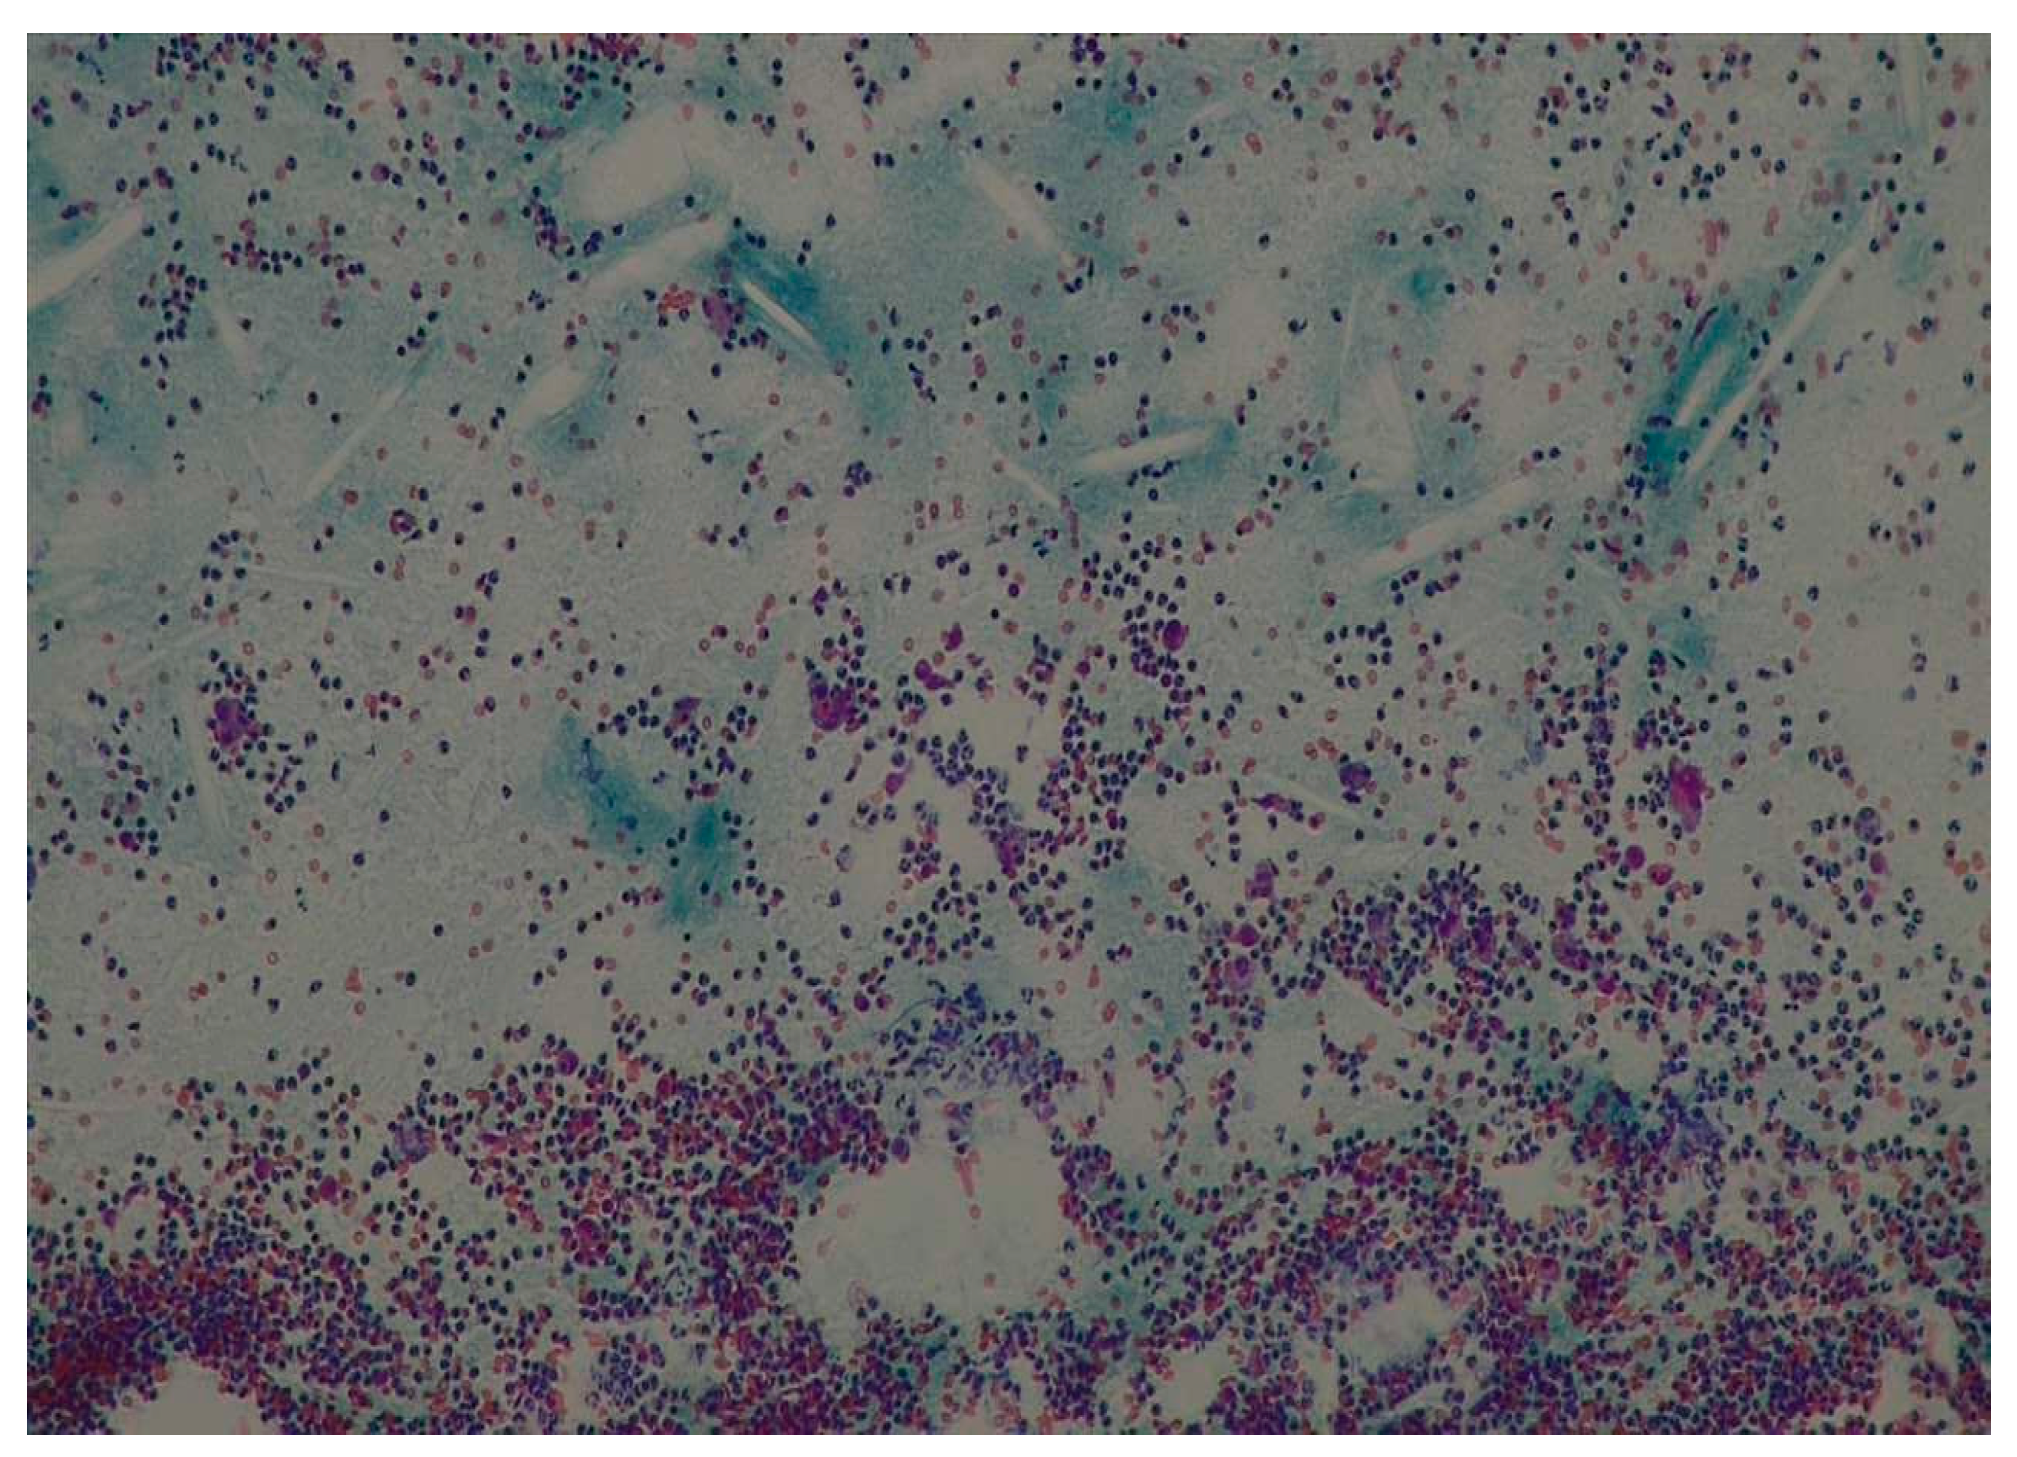

- Goyal, S.; Sharma, S.; Kotru, M.; Gupta, N. Role of FNAC in the diagnosis of intraosseous jaw lesions. Med. Oral Patol. Oral Y Cirugía Bucal. 2015, 20, e284. [Google Scholar] [CrossRef] [PubMed]

- Permi, H.S.; Sunil, K.Y.; Sajitha, K.; Kishan, P.H.; Teerthanath, S.; Jayaprakash, S.K. A prospective study of fine needle aspiration cytology of intraoral lesions. J. Evol. Med. Dent. Sci. 2015, 4, 14777–14787. [Google Scholar] [CrossRef]